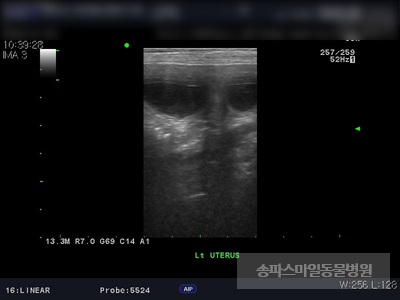

초음파 검사상 자궁의 크기가 매우 확장되었으며 자궁 내부의 액체가 고여있는 것으로 확인되었습니다.

강아지 자궁축농증이 진단되었습니다.